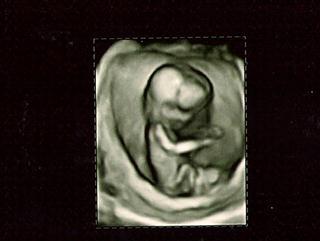

Zurück vom FA und total verliebt ♥. Es ist alles in Ordnung mit unserem Krümel. NFM war unauffällig, Organe alles in Ordnung. Sie tippt auf einen Jungen, aber will sich natürlich noch nicht festlegen. Ist jetzt 11,8 cm groß und wiegt 85 gr, bin lt. Ultraschall bei 13+0, eigentl. bei 13+4! Hach war das schön und das Herz haben wir schlagen hören. Hier noch 2 Bildchen!

Bild zu FA Termin von gestern - Forum für August - Mamis

Hier noch ein Foto von unserem Engel.

Bild zu